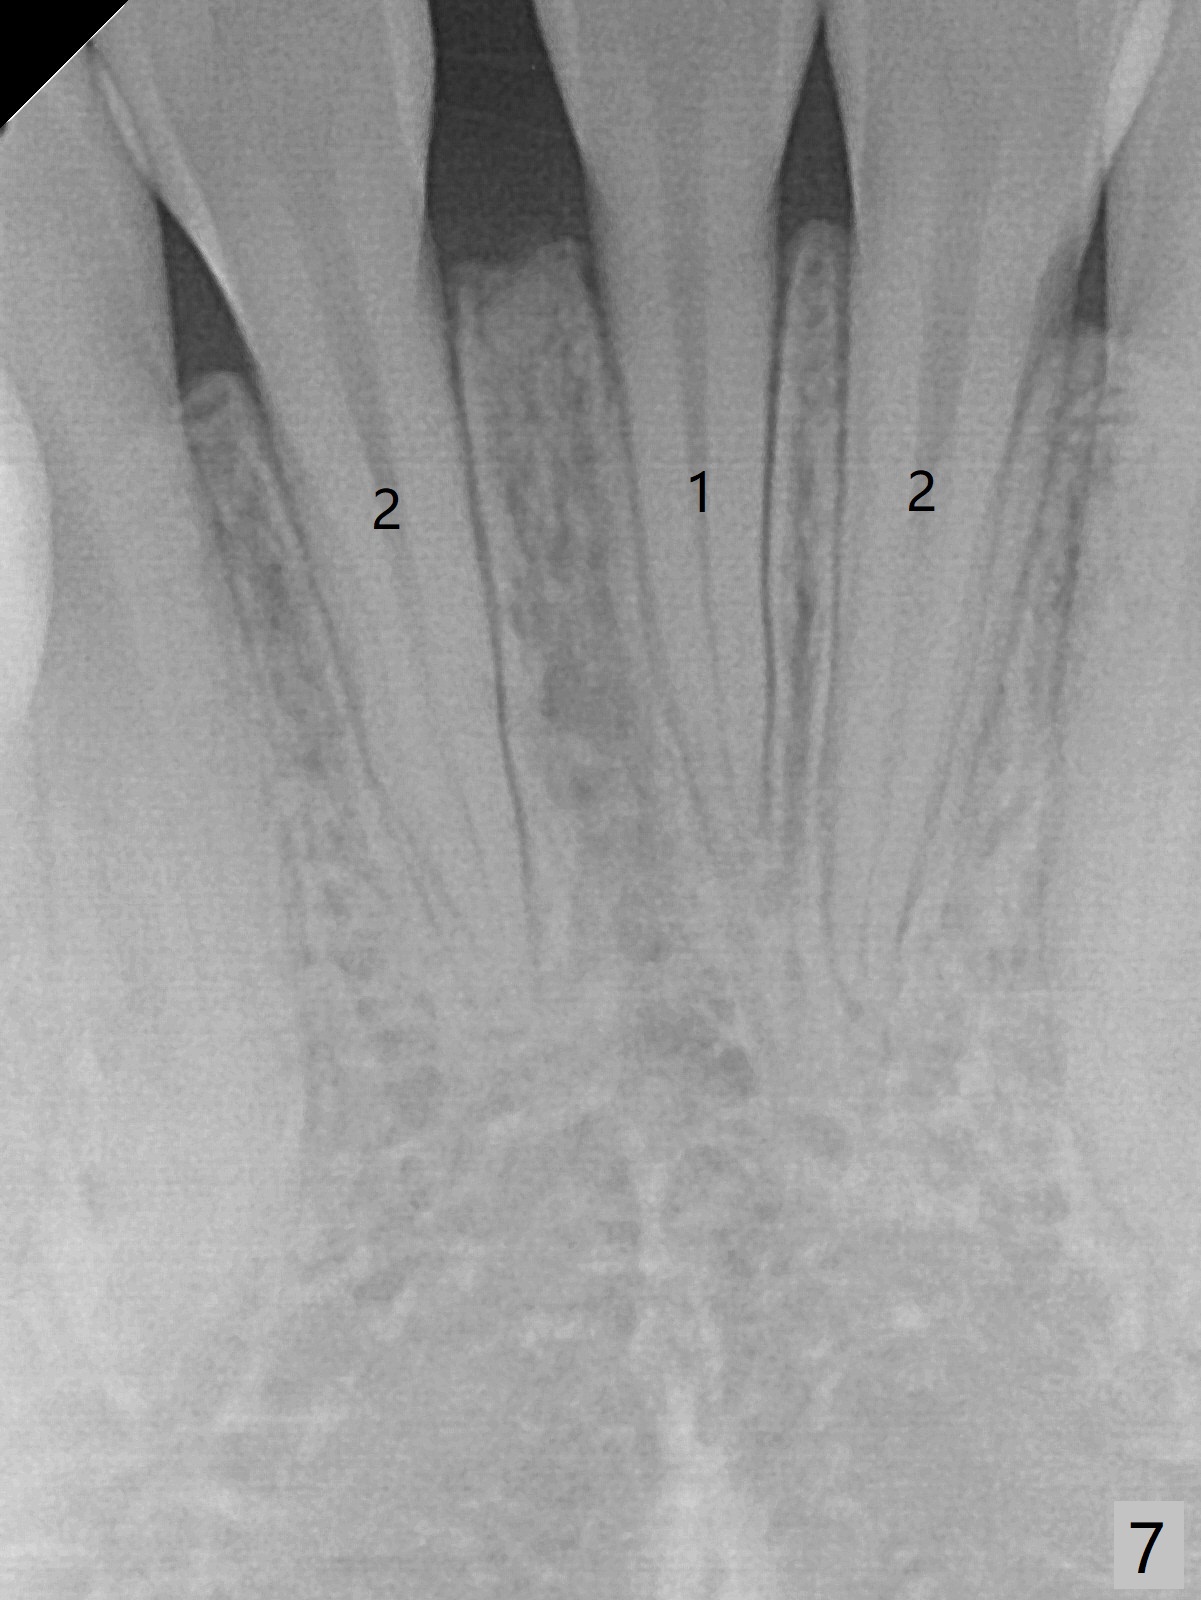

13岁女孩面型正常,先天性缺失右下1(图一,四,七),前牙深覆盖(图二),邻牙扭转(图三),治疗计划使用隐形矫正器,上牙片切,内收,关闭下切牙间隙(图八)。片切前发现上切牙邻面龋(图五,六),最大一个已经修补(右上2),不知其余小的龋坏能否片切,涂氟保守处理?不过她有龋坏易感性,以前乳牙龋坏。邻面片切后,上,下颌分别用无色和蓝色树脂做attachments(图九)。不明白的是Reciprocating saw远不如wheel利索。